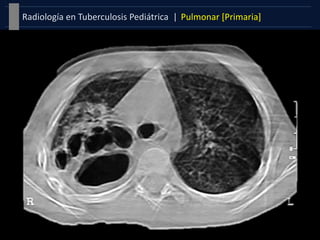

Derrame pleural

 Secuela tardía de infección

primaria (3-7 meses tras la

exposición).

 Generalmente unilaterales y

ecograficamente presentan

septos producidos por el

exudado tuberculoso.

 Patrón más característico de

la en el adolescente.

Formas Clínicas |Pulmonar [Primaria]Tuberculosis Pediátrica | Derrame pleural  Secuela tardía de infección primaria (3-7 meses tras la exposición).  Generalmente unilaterales y ecograficamente presentan septos producidos por el exudado tuberculoso.  Patrón más característico de la en el adolescente. Patrón Miliar  Patrón intersticial de una diseminación hematógena pulmonar.  Nódulos finos, >2mm, márgenes bien definidos, uniformes en tamaño y distribución, sin tendencia a confluir, y diseminados de forma homogénea y bilateral.  Hiperinsuflación manifestación más temprana (dos primeras semanas).  El nódulo miliar puede no ser visible en la radiografía hasta seis semanas después.